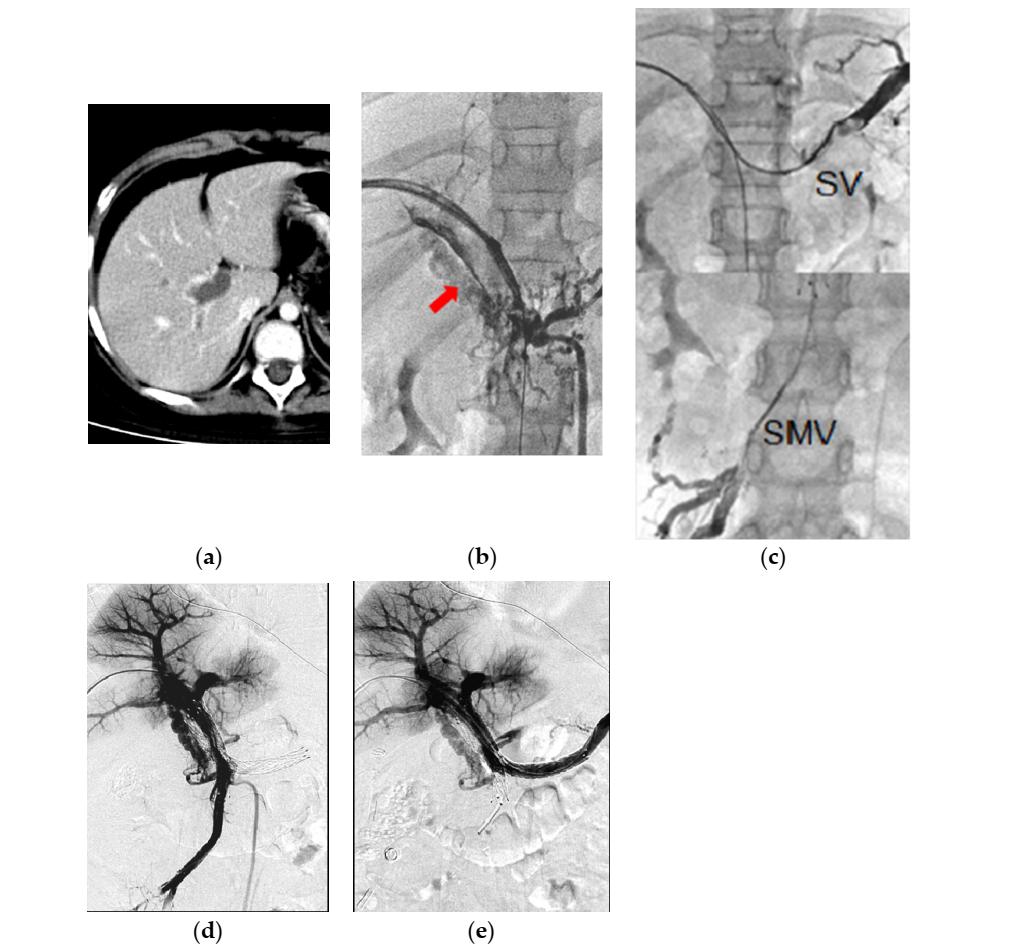

(图源自文献)

一例慢性PMVT患者,女,9岁,肾病综合征,主诉为间歇性腹痛6个月。

a

CT显示弥漫性PMVT。

b

经皮肝穿刺PV造影证实CT表现。箭头:PV海绵样变。

c

上部:脾静脉(SV)血栓。下部:SMV血栓。

d,e

经皮肝穿刺PV造影显示:经连续输注UK(12天总剂量为680万IU)、BMS放置、反复球囊扩张,SMV、SV、PMV、肝内PV均再通。术后128个月随访行彩色多普勒超声,检查血管通畅性。